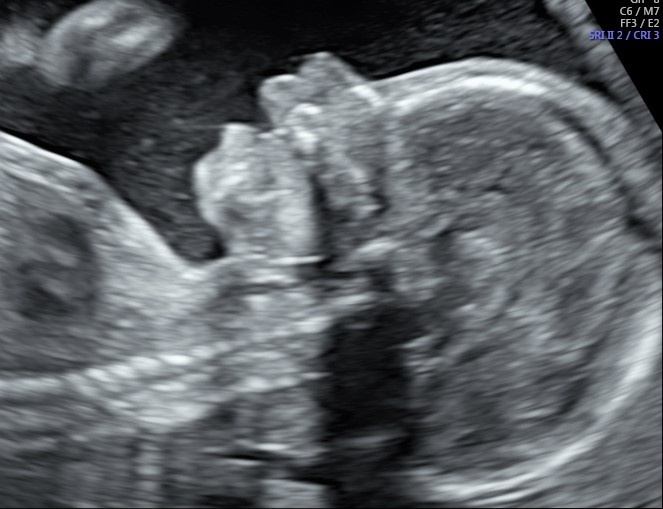

Il nostro tesoro comincerà a prendere forma dalle mani dell’ecografista che ci descriverà come è fatto, quanto grande è, e soprattutto come sta.

L’indagine è una visione sistematica dalla testa ai piedi del bambino, le sue misure con il calcolo del peso e la valutazione del suo benessere basandosi sui movimenti, Il liquido amniotico ed alcuni parametri vascolari investigati con la doppler flussimetria, come il dotto venoso.

L’ecografia morfologica, come tutte le ecografie ostetriche, deve dare ampio spazio anche ai genitori, alle loro curiosità, al loro bisogno di essere rassicurati, ed è da questa settimana che si possono fare delle bellissime foto in 2D e 3D del volto del piccolo, sia frontalmente che di profilo, innescando invariabili conflitti sulle presunte somiglianze. Se non abbiamo eseguito l’ecografia pre-morfologica, è questo il momento in cui finalmente abbiamo la conferma se il piccolo è une “tesorino” (sinistra) oppure una “tesorina” (destra).